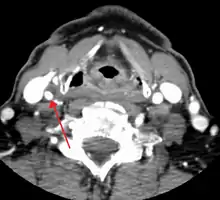

Carotid artery stenosis is usually diagnosed by color flow duplex ultrasound scan of the carotid arteries in the neck. This involves no radiation, no needles and no contrast agents that may cause allergic reactions. This test has good sensitivity and specificity.[16]

Typically duplex ultrasound scan is the only investigation required for decision making in carotid stenosis as it is widely available and rapidly performed. However, further imaging can be required if the stenosis is not near the bifurcation of the carotid artery.[17]

One of several different imaging modalities, such as a computed tomography angiogram (CTA)[18][19][20] or magnetic resonance angiogram (MRA) may be useful. Each imaging modality has its advantages and disadvantages - Magnetic resonance angiography and CT angiography with contrast is contraindicated in patients with chronic kidney disease, catheter angiography has a 0.5% to 1.0% risk of stroke, MI, arterial injury or retroperitoneal bleeding. The investigation chosen will depend on the clinical question and the imaging expertise, experience and equipment available.[21]